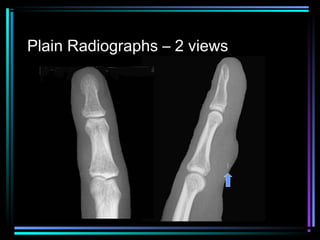

Plain Radiographs – 2 views

Posterior

Dislocation